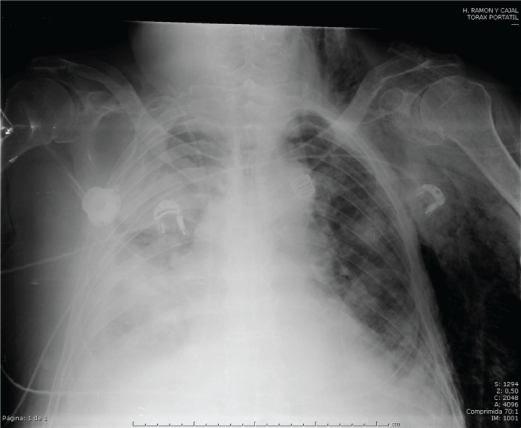

Subcutaneous emphysema occurs when air gets into tissues under the skin. It occurs mainly in the neck, chest and face when air travel to these areas of the chest cavity through the fascia. Introducing the chest radiograph of a 73 year old male diagnosed with chronic pericardial effusion mass, intervened on a scheduled basis for pericardial window, and in the immediate postoperative period presents important in left chest subcutaneous emphysema associated with desaturation and tachycardia. Suspecting possible pneumothorax that can not be clearly distinguished in the test image, and the likely need for intubation to the serious clinical condition, chest tube placement, which successfully produces clinical improvement and patient decide. The main causes that we suspected in a subcutaneous emphysema are pneumothorax, broken tree traqueobronquial [1], esophageal rupture, necrotizing infections and dental procedures using air comprimido [2] elements, and to the possible need for applying positive pressure to the patient, as in this case , we will place a chest tube though not clearly distinguish the camera radiographic pneumothorax.

Figure 1: Pneumothorax and subcutaneous emphysema